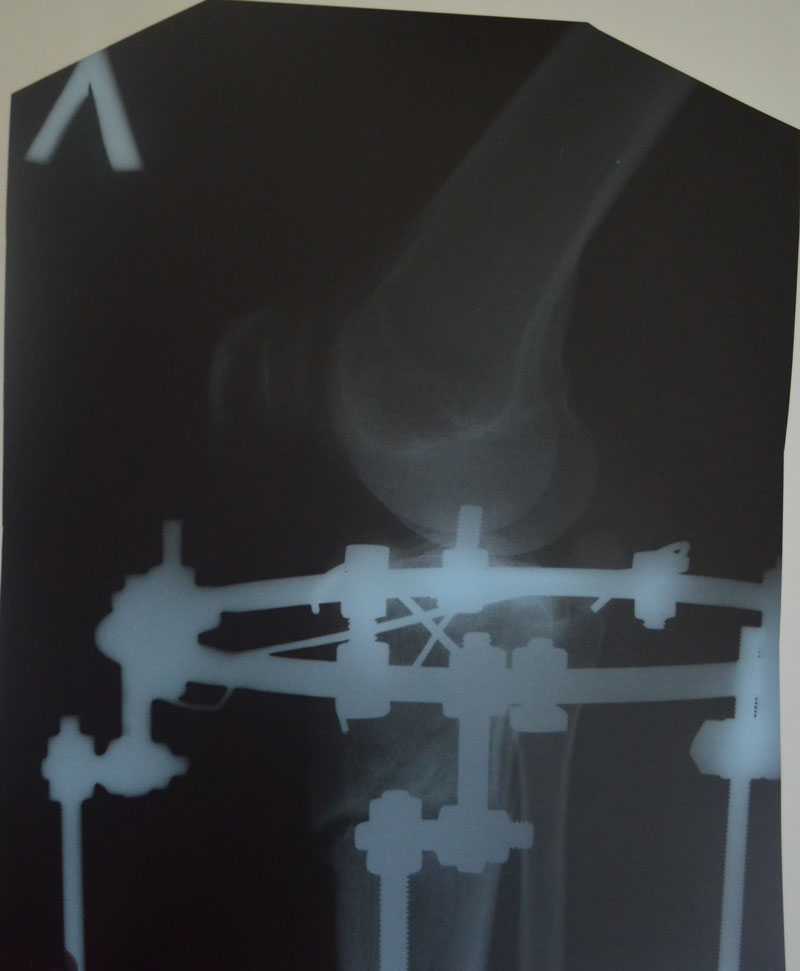

- Диагноз: О-образная деформация нижних конечностей

Всё хорошо, ножки ровные, продолжаем фиксацию!

По рентгену, ось ровнейшая. Правая срослась, а левая... Ходить Вам ещё минимум 3 недели, после делайте ещё рентген и отправляйте по эл. почте. Начинайте принимать препараты кальция и мумиё - его нужно принимать так: развести в 0,5 л. банке 10 таблеток - мумиё, до полного растворения таблеток. После этого, принимать по 1 ст. ложки раствора 3 раза в день. Хранить в холодильнике.